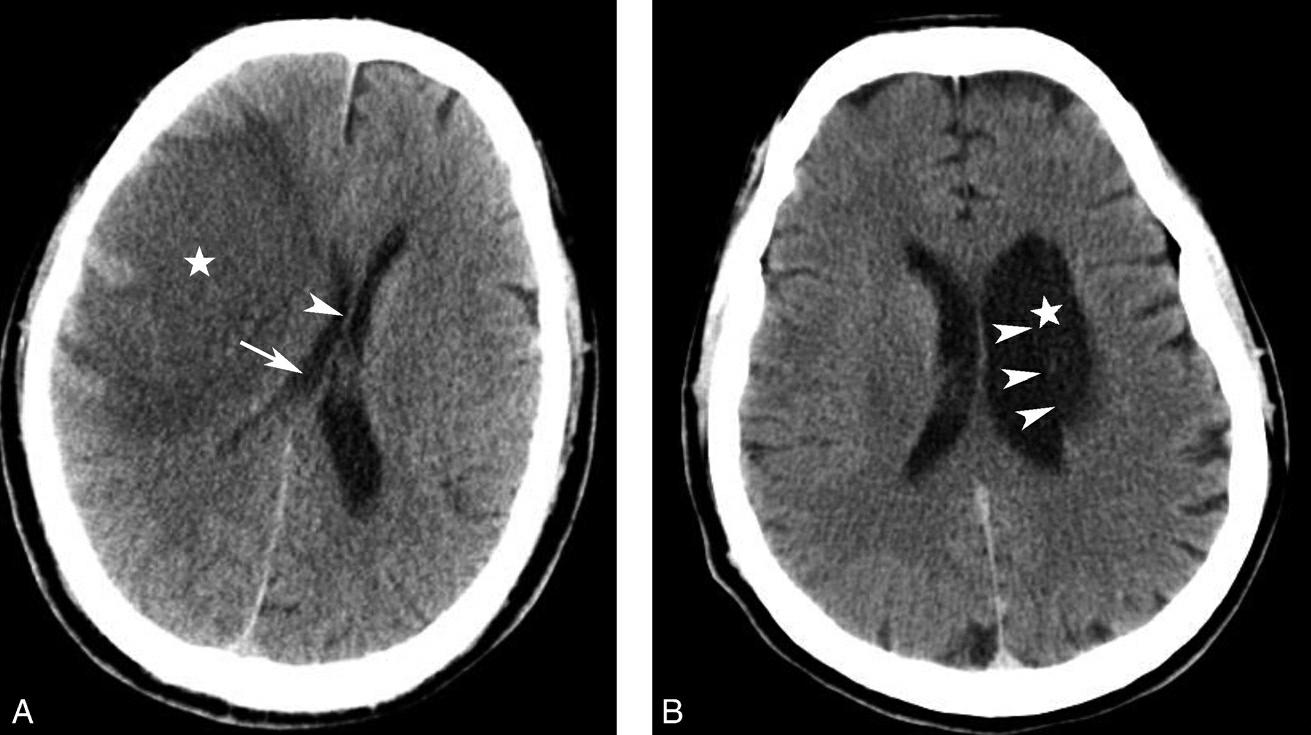

图1-2-14 静脉窦增宽、密度升高(静脉窦血栓)

男,47岁,头痛2周,意识模糊2天,无头颅外伤史。A.CT平扫示双侧横窦增宽、密度增高(黑箭),提示静脉窦血栓;B.MRI T 1 WI提示双侧乙状窦、横窦血栓形成(白箭)